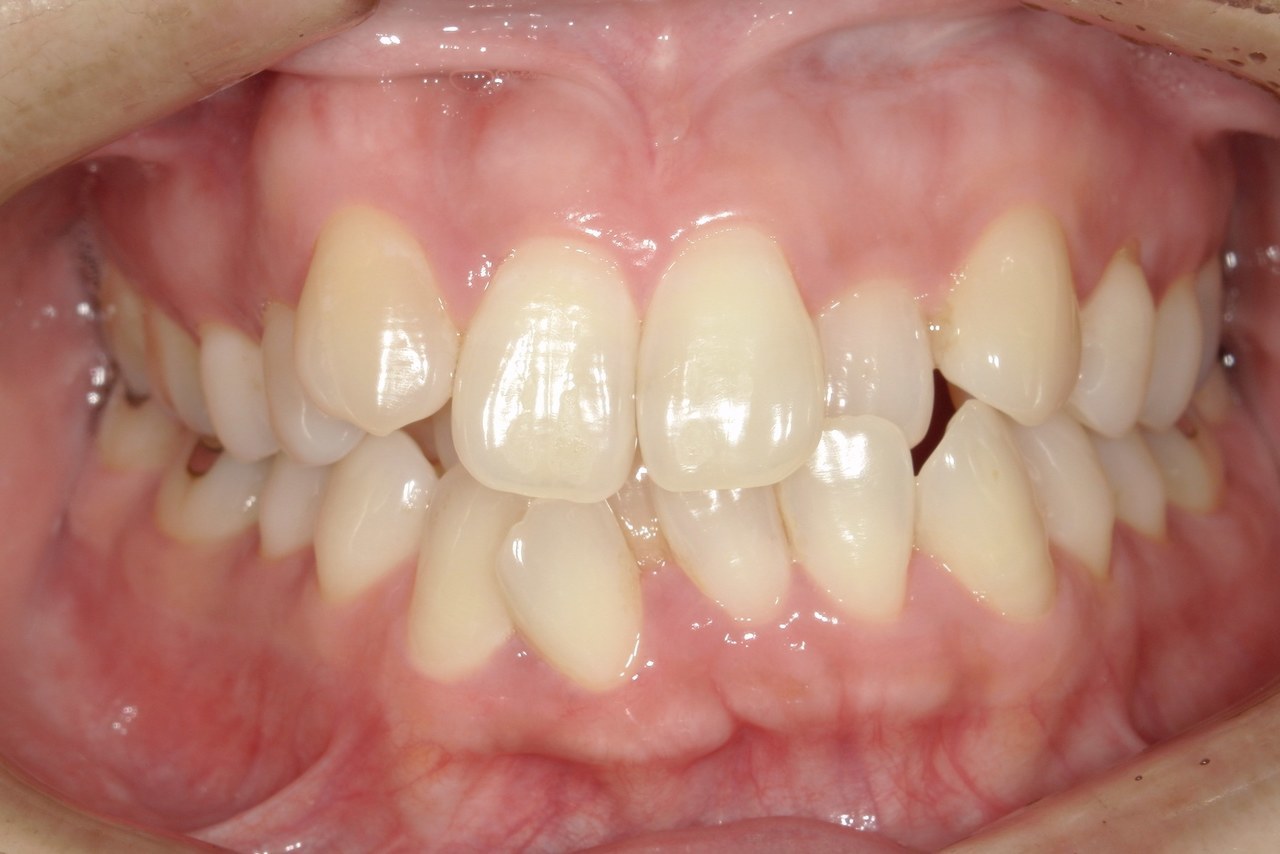

Before

浜松市中央区・自動車学校前駅のインビザラインの症例

K.M 20代女性

上の前歯が前方に出ていて横顔が気になるとの主訴でご来院。上下犬歯から犬歯までの6本が噛み合うよう、全体的に歯を内側に移動させることで、前歯の噛み合わせを整え叢生と開咬を治療しました。

​治療の期間:R5. 7/5〜R7. 1/17

​治療の価格:66万円